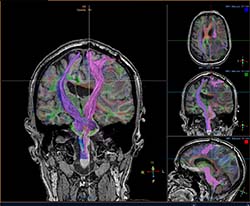

neuroradiology exam image

Residents submit hundreds of cases to the AIRP, but only a handful are designated as the course's best cases.

View a selection of the best cases selected from a recent radiologic-pathology course.